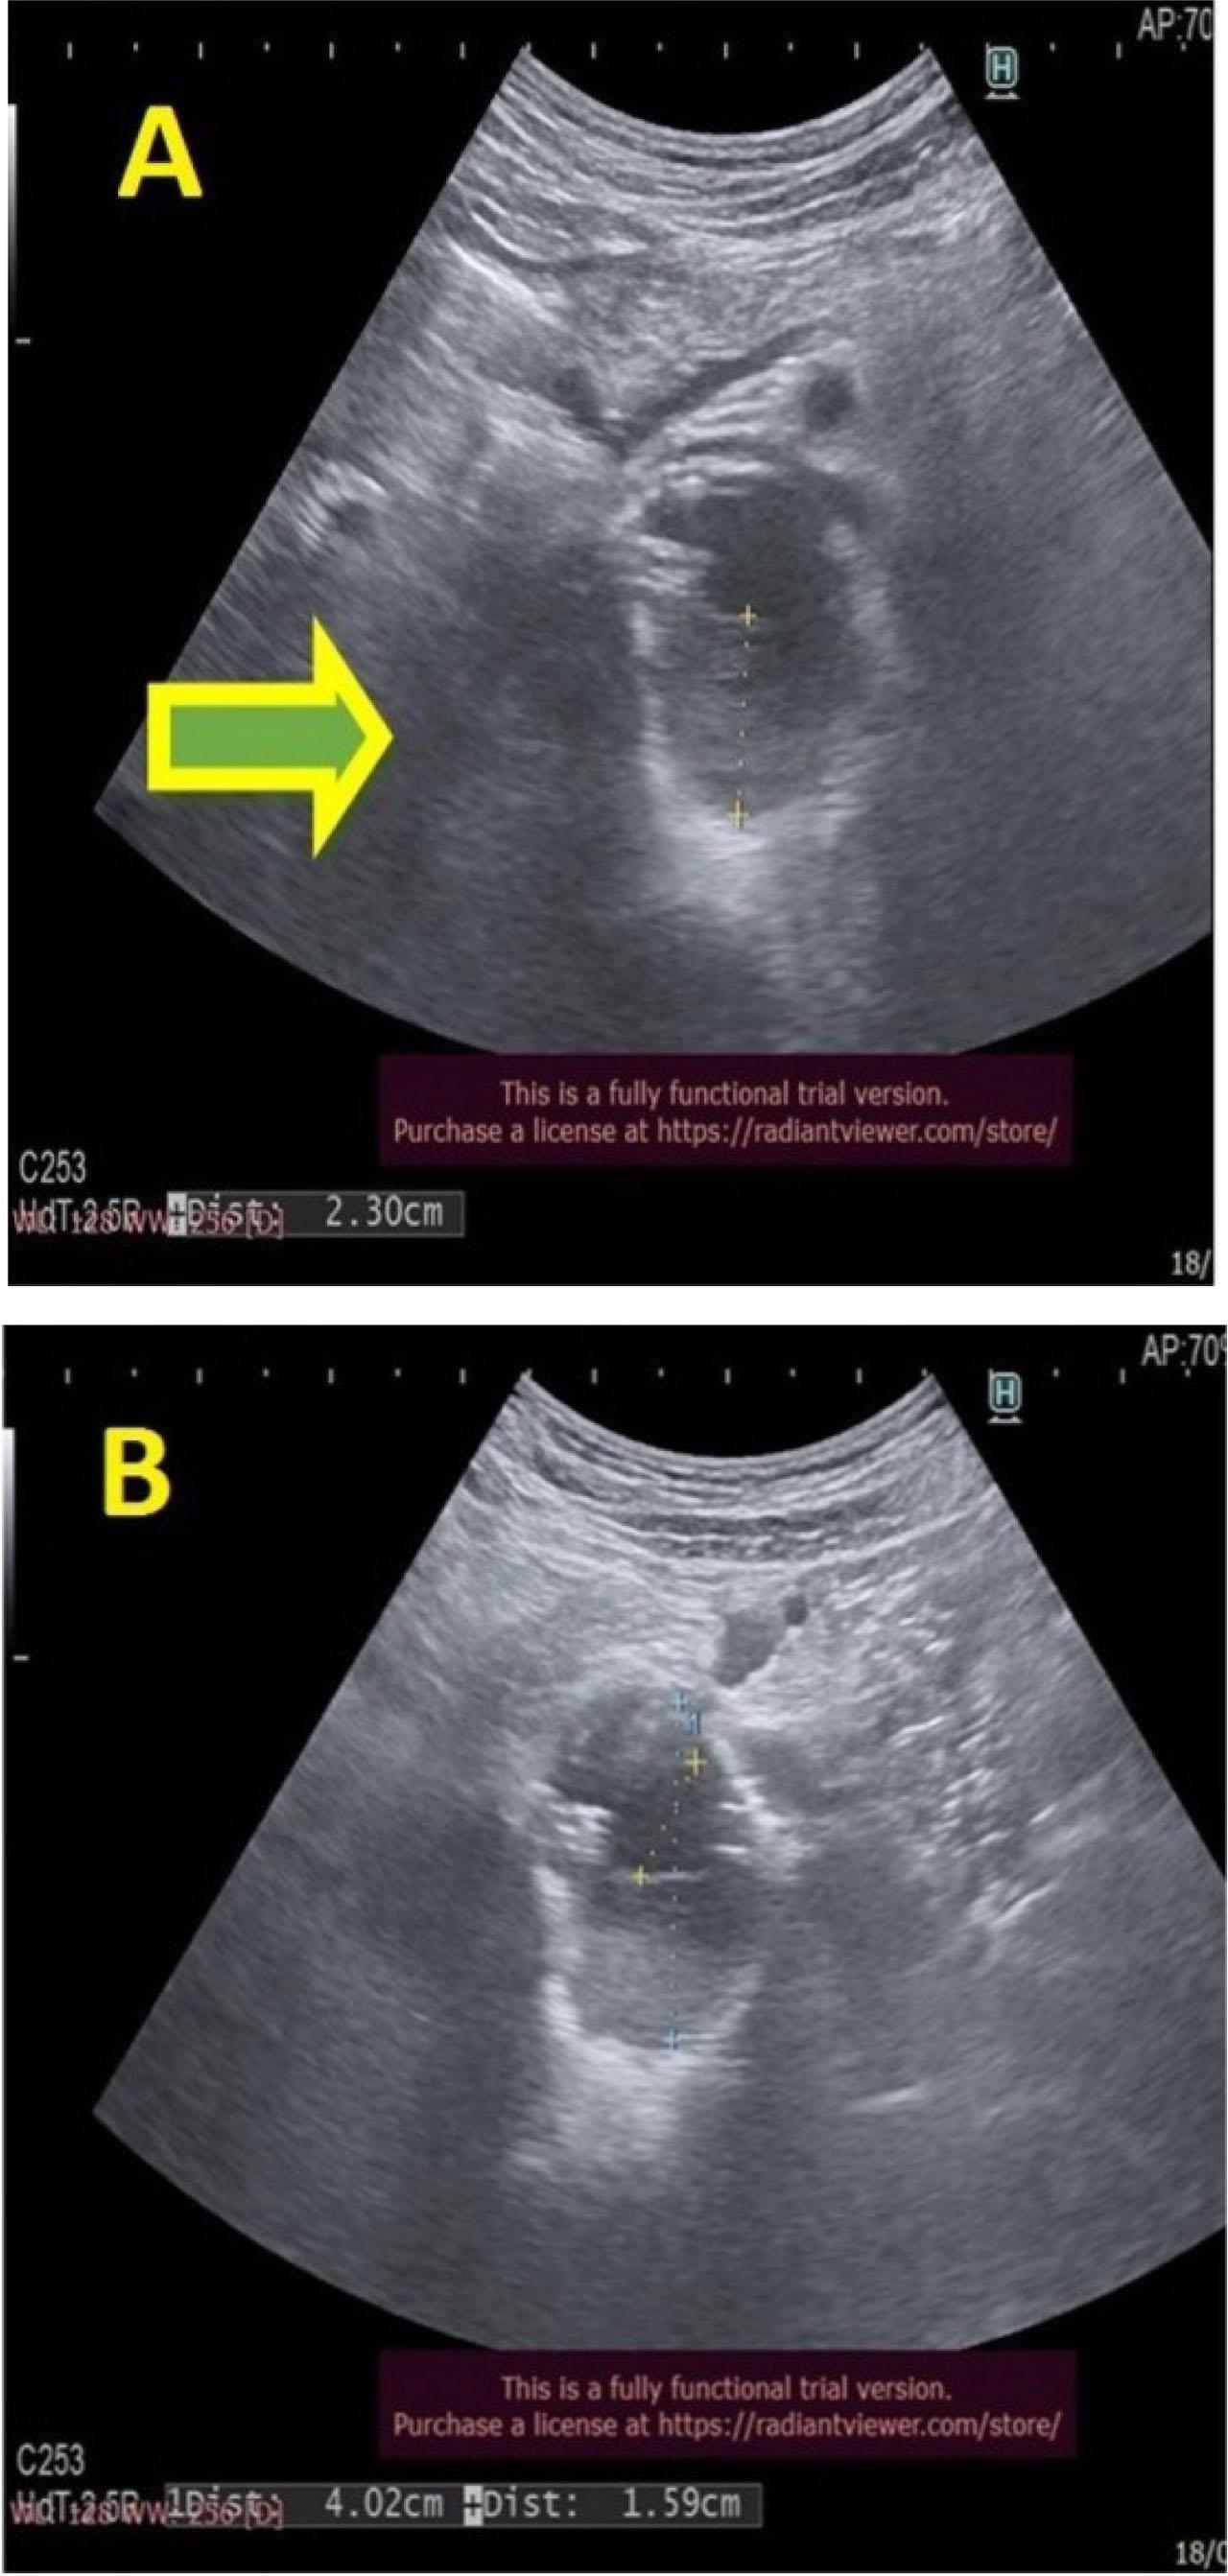

The abdominal echography objectified the persistence of thrombosed aneurysm in the abdominal aorta, with the appearance of a hyperechoic mass attached to the posterior wall of the aorta, which causes a significant obstruction of approximately two thirds of its lumen (Figure 4A). The patency of the renal arteries ostium is noticeable, observing even the proximal extremities of the stents at this level (Figure 4B), which protrude in the aortic lumen, with flow present at the Doppler examination.

Abdominal ultrasound: descending aortic thrombosis and patent renal artery stents.